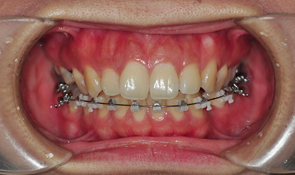

이렇게 장치 재부착을 완료하였습니다.

도착후 전체적인 점검을 하고 기존에 걸어 놓았던 와이어를 꺼냈습니다. 우와웅 한달밖에 안됫는데도 와이어에서 시간의 흔적이

와이어를 꺼낼때느 뭔가 시원한 느낌이 들더라구요 해체하는 기분 ㅋㅋㅋㅋ 와이어 없을때 얼른 사진 하나 찍었어요 쿄쿄

뭔가 2% 부족한 느낌,,